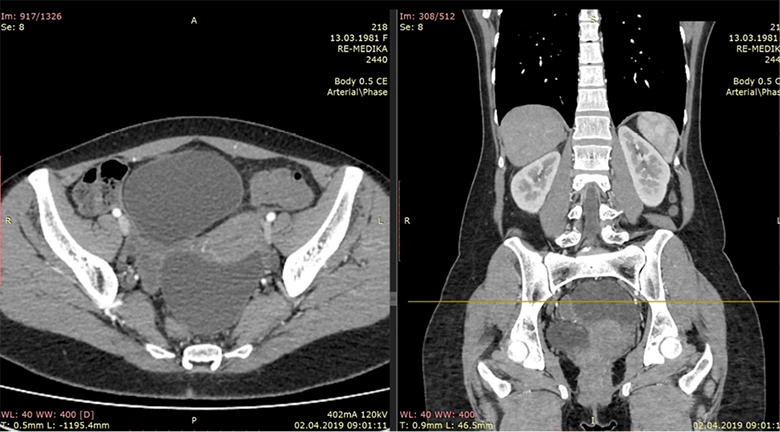

An CT scan of the abdomen was performed and were found two cystic liver formations, also a cystic formation was verified in the pelvis. The native series of the abdominal CT have shown a segment II and IV hepatic per-magna cystic formations with dimensions: No I: 80×60×74 mm (Figure 1) and No. II: 70×60×58 mm (Figure 2). The changes are with a pericystic reaction of a hypodense character. The formation in the second hepatic segment had a visible mass effect on the stomach. In post contrast series, cystic liver formations were shown as hypodense, hypovascular structures with a clearly expressed contrast accumulation in the cystic membrane and with a demarcation of the pericystic reaction. Per magna cystic formation with hypodense character was also detected at the level of the small pelvis, retrouterine, in the Douglas space, with dimensions of 93×90×62 mm (Figure 3). The cyst has a clearly expressed mass effect on surrounding organ structures. Utter in the AVF pressed to the left. The liver cystic formations were with characteristics of Ehcinococcal cyst but with no serological verification.

Figure 3. Hypodense cystic formation in small pelvis